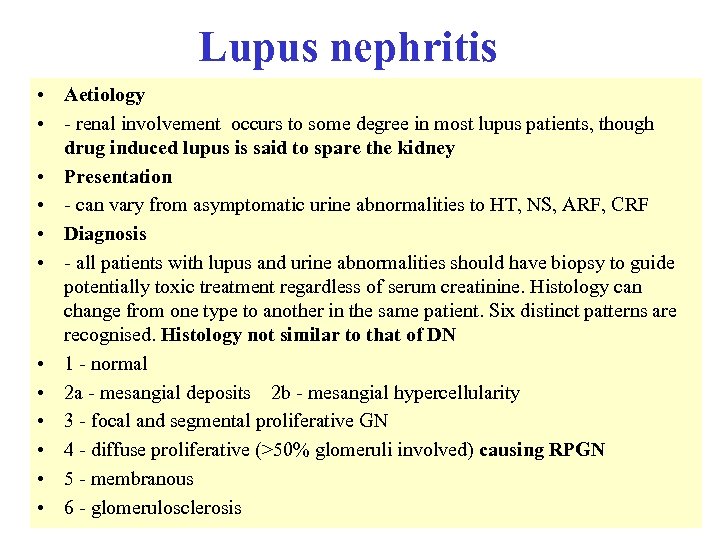

Reduced serum complement • • Occurs in: - SLE - infective endocarditis - post strep nephritis - shunt nephritis - cholesterol embolism - cryoglobulinaemia - MCGN types 1 and 2 • • Complement normal in FSGS, amyloidosis, Alports, anti GBM disease C 3 nephritic factor is an Ig. G auto antibody to the C 3 convertase of the alternative pathway of complement activation, found in both types of MCGN